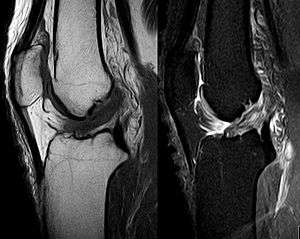

The pivot-shift test, anterior drawer test, and Lachman test are used during the clinical examination of suspected ACL injury. The Lachman test is recognized by most authorities as the most reliable and sensitive test, and usually superior to the anterior drawer test.[11] The ACL can also be visualized using a magnetic resonance imaging scan (MRI scan).

Though clinical examination in experienced hands can be accurate, the diagnosis is usually confirmed by MRI, which has greatly lessened the need for diagnostic arthroscopy and which has a higher accuracy than clinical examination. It may also permit visualization of other structures which may have been coincidentally involved, such as a meniscus, or collateral ligament, or posterolateral corner of the knee joint.